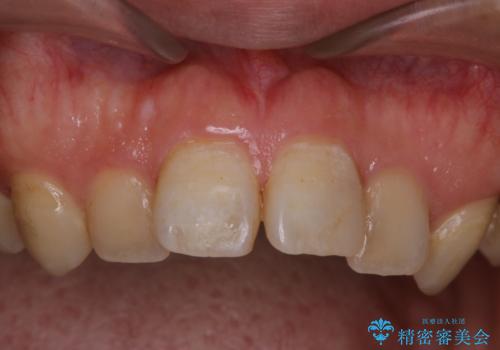

- インビザライン矯正治療の開始前にキレイな状態にしたいとのことでした。PMTC30分コースを行ってからインビザラインの型どりを行いました。

インビザラインの型どり・スキャニング(光学3Dスキャナー「iTero Element」)の前に、プラークや歯石・ステインを除去することで、ご自身本来の歯の状態となるため、綺麗なスキャニングが行えます。より精度のよいマウスピースを作成するために、PMTCを行うことをおすすめしています。